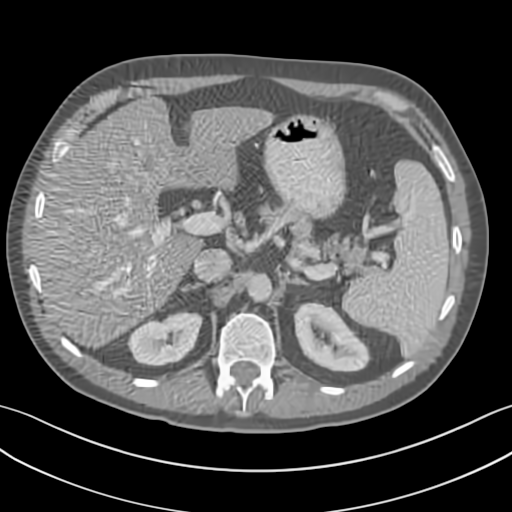

To demonstrate the effectiveness of the proposed network, we perform the qualitative comparisons over three representative abdominal images presented in Figs. 3, 5 and 7. For better evaluations of the image quality with different denoising models, zoomed regions-of-interest (ROIs) are marked by red rectangles and shown in Figs. 4, 6 and 8 respectively. Note that all results from different denoising models focus on two aspects: content restoration and noise-reduction. All CT images in axial view are displayed in the angiography window [-160, 240]HU.

The real NDCT images and corresponding LDCT images are presented in Figs. 3a and 3b. As observed, there are distinctions between ground truth (NDCT) images and LDCT images. Figs. 3a and 7a show the lesions/metastasis. Fig. 5a presents focal fatty sparing/focal fat. In Figs. 4a, 6a and 8a, these lesions can be clearly observed in NDCT images; in contrast, from Figs. 4b, 6b, and 8b, it can be seen that the original LDCT image is noisy, and lacks structural features for task-based clinical diagnosis. All adopted denoising models suppress noise to some extent.